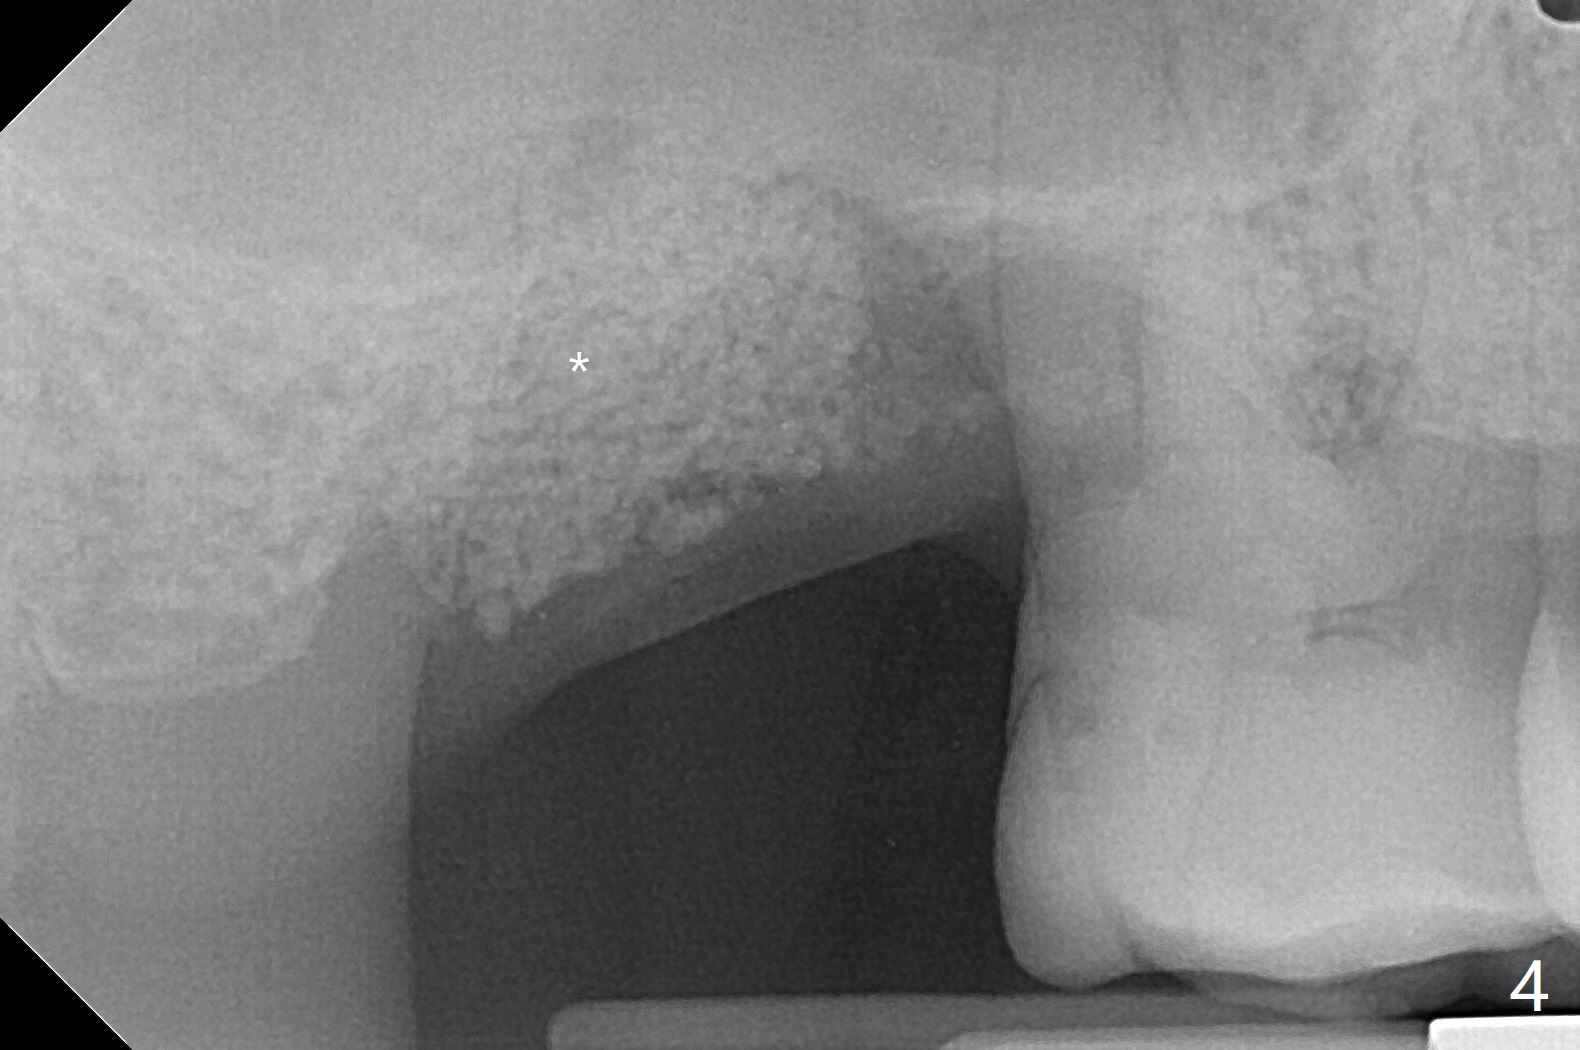

50岁男,二型糖尿病,对常用糖尿病药物无效,使用胰岛素也必须提高剂量,总之控制不好。总共种植四个,两个延期没问题,但是两个即刻均失败,似乎容易发炎,包括右上7(图一:* (螺纹暴露)),颊侧牙龈退缩(图二),牙冠取出后显示植体和基台偏腭侧(图三:P),其实植体没有整合,不费劲旋出植体,清除肉芽组织后,植入粘性骨粉(图四:*),覆盖PRF膜,GEM Cap,应用牙周胶水固定,然后间隙维持器,牙周敷料固位。右上7和左上7植牙取出后4个月和一年5个月骨质高度很低(图五)。右上7大约1.8毫米(图六)。准备植入5x7毫米植体(图七)。使用1毫米stopper钻头,然后Magic Lifter和PRF。术前口服Z Pack,术后Medrol Dose Pack。